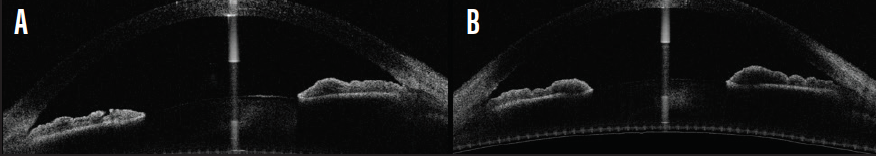

At a recent examination, IOP was 16 mm Hg OD and 19 mm Hg OS. The referring optometrist found the angles to be closed for 180º and narrow, with only anterior trabecular meshwork visible over the remaining 180º in each eye. Anterior segment OCT (AS-OCT) confirmed that there was no pupillary block component and that the iridotomies were patent (Figure 3). OCT imaging showed worsened inferior thinning of the left optic nerve (Figure 4), and new visual field deficits were present in the left eye (Figure 5). The patient used the Icare Home tonometer (Icare USA) to measure her IOP several times daily over the course of a week; the unit detected IOP fluctuation, with maximum readings of 24 mm Hg OD and 34 mm Hg OS (Figure 6).